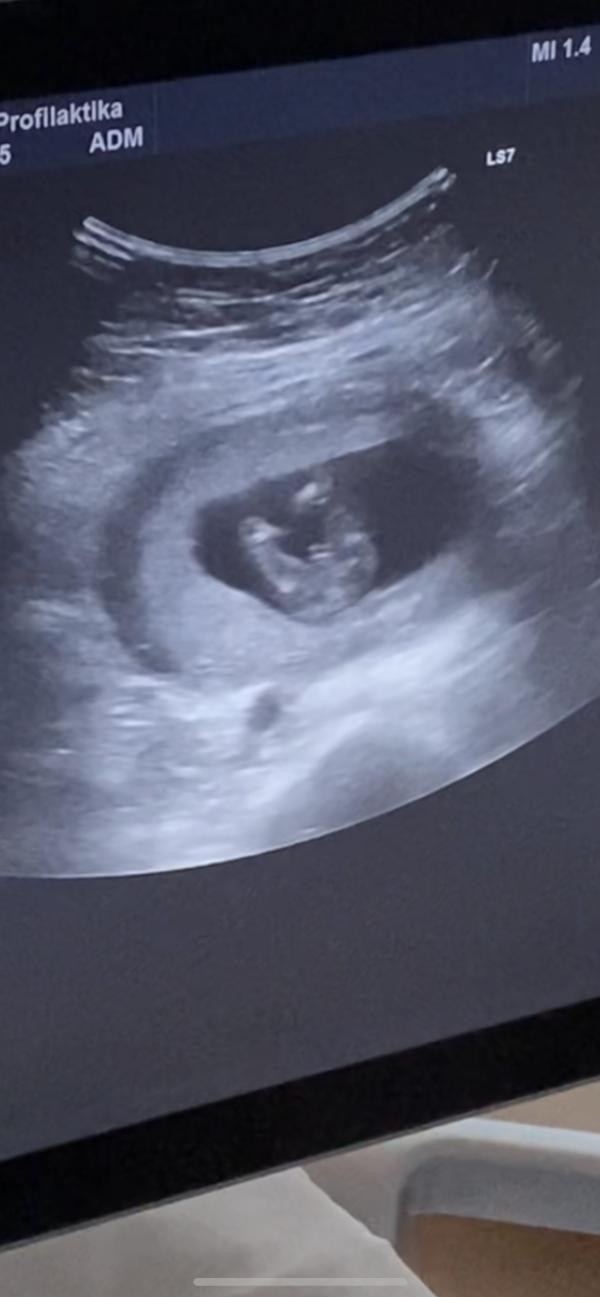

Опытные мамочки и все, кто разбираются, нужна ваша помощь☺️ Была сегодня на УЗИ, срок 14 недель. Сказали, что очень похоже на мальчика, но это неточно. Подскажите, может ли быть девочкой? Всю жизнь была уверена, что дочка будет. Заранее всем спасибо 🙏🏻

Точь в точь фотка в 12нед с дочкой. У них клитор торчит ,надо смотреть под углом а не между ног.

Я в 13 недель на скриненге смотрела на такую же фотку, только у меня девчуля, а тут явный мужичек.....,

@evstolia0788 пуповина длинная... Её не перепутать с бубенцами🤭

@gulya33, @mirpl210391, @nyushka_5, 🙏🏻 Эх, я уже поняла, но капелька надежды теплилась. Все пыталась кофейное зернышко разглядеть))

Мальчик